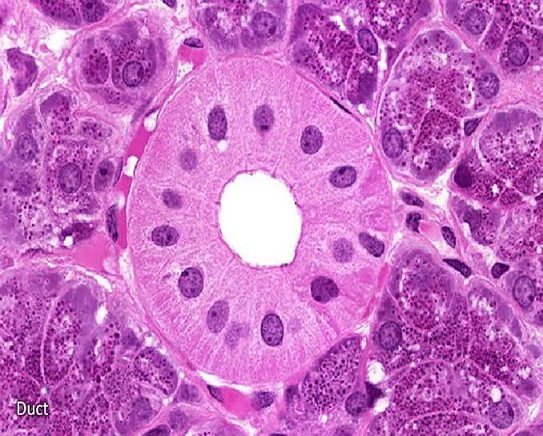

Histopathology

Increasing incidences of cancers can’t be ignored now a days and we all know the importance of correct and timely diagnosis of cancer. We have in house unit which include world class euipments for processing the tissue and prepare slides for detailed examination by expert pathologist.

We also perform Immunohistochemistry and Molecular testing which are very important for diagnosis, prognosis and in deciding therapy.

Histology

Our SANAS accredited histology laboratory offers a diagnostic service to both the private and public sectors. Our large team of anatomical pathologists, technologists and technicians, with vast amounts of experience offers a diagnostic and consultative service on a number of tissue samples including biopsies and resection specimens.

- Immunocytochemistry

- Immunofluorescence

- Electron Microscopy

- Neuropathology

Cytology

Aside from tissue biopsy, cytology serves as an indispensable tool in screening and diagnosing cancer. In this technique, a cytological material is obtained from the patient, spread onto glass slides for microscopic examination, stained, screened for abnormalities and assessed prior to the issuance of a final report.

- Gynaecological Cytology

- Non-Gynaecological Cytology

- Fine Needle Aspiration Cytology

- BAL Differential Cell Count